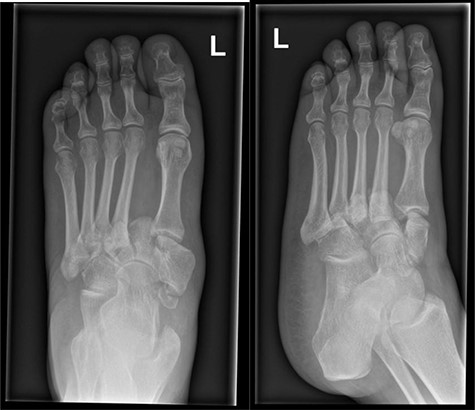

At this presentation, plain film X-ray revealed complete fracture dislocations of the second to fifth tarsometatarsal joints, involving the lateral, middle and medial cuneiform bones of the left mid-foot (Lisfranc fracture dislocations; Fig. 3). This was correlated with bone CT (computed tomography) and MR (magnetic resonance) imaging, with interval changes noted to be of rapid onset (Fig. 4).

Foot X-rays taken at acute presentation (AP and lateral views), demonstrating rapid interval progression and destruction to mid-foot.